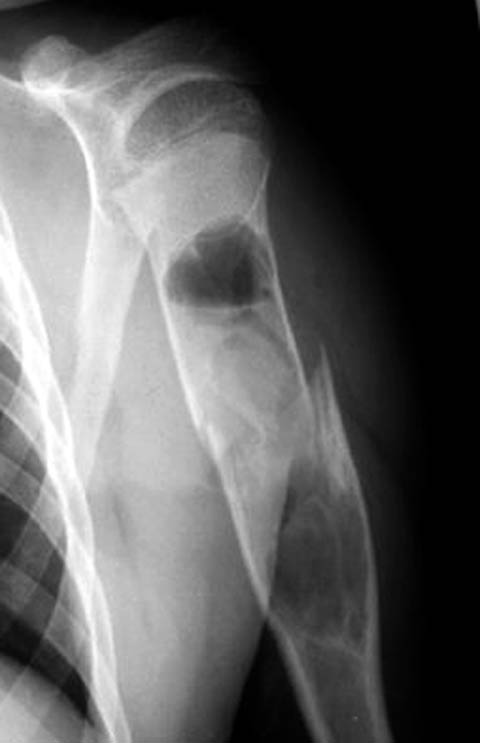

Дифференциальную диагностику надо проводить между однокамерной костной и

аневризмальной кистой, но расположение в полости кисты тонкого,

линейного фрагмента кости, подтверждает диагноз однокамерной

костной кисты.

"Упавший" фрагмент - патогномоническая подсказка к патологическому

перелому, часть стенки падает в полость кисты и опускается вниз из-за

силы тяжести.

Подозрение о "шаровидной полости" в головке - это из-за укладки,

и на представленном снимке подтверждение правильности рекомендации коллег.